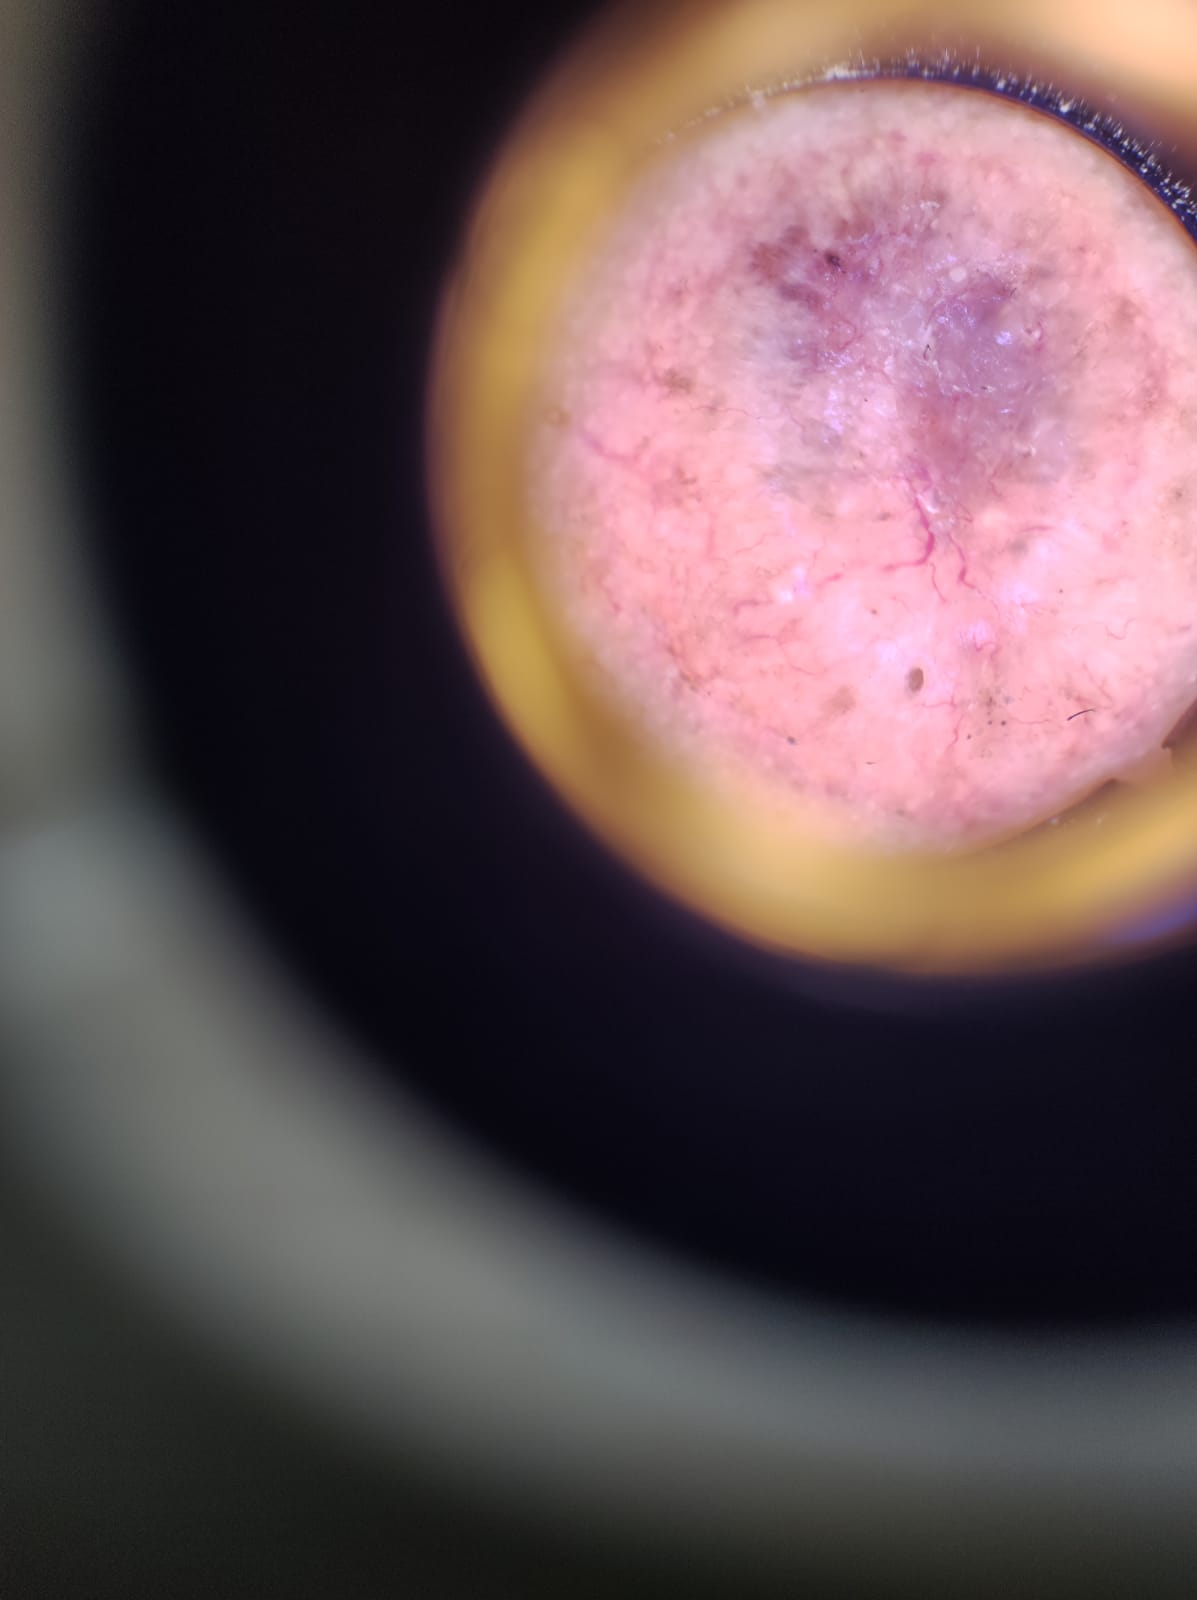

La 11ª JORNADA DEL LUNAR que se llevó a cabo el día 23 de julio de 2023, fue un éxito. Se atendieron pacientes en los diferentes lugares de atención, haciendo una evaluación de todas las lesiones pigmentadas (lunares) y todas aquellas sospechosas de malignidad fueron referidas a los diferentes centros asistenciales para su estudio y tratamiento por Médicos Dermatólogos afiliados a PRODERMA y a los Médicos Oncólogos afines a nuestra Asociación.